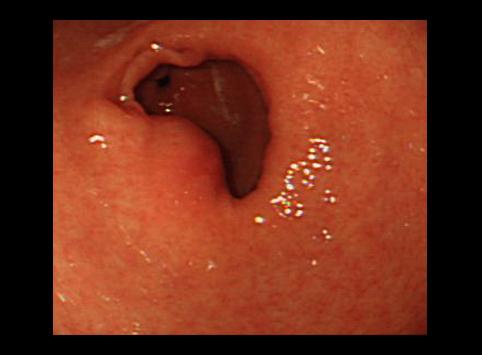

질환(병리주체)의 분류 종양양 병변/이소성 점막

부위(장기별) 위(부위)/전정

검사방법 내시경

종양의 최대경(밀리미터) 30~34